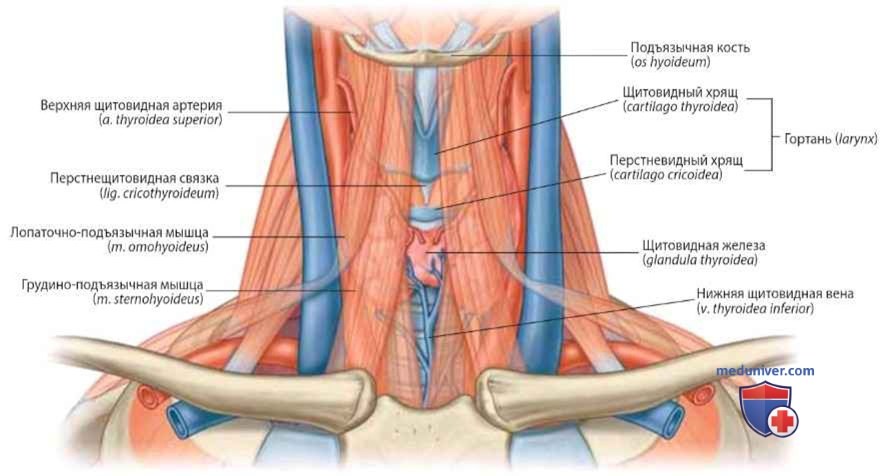

Анатомия внутренней яремной вены: КТ изображения